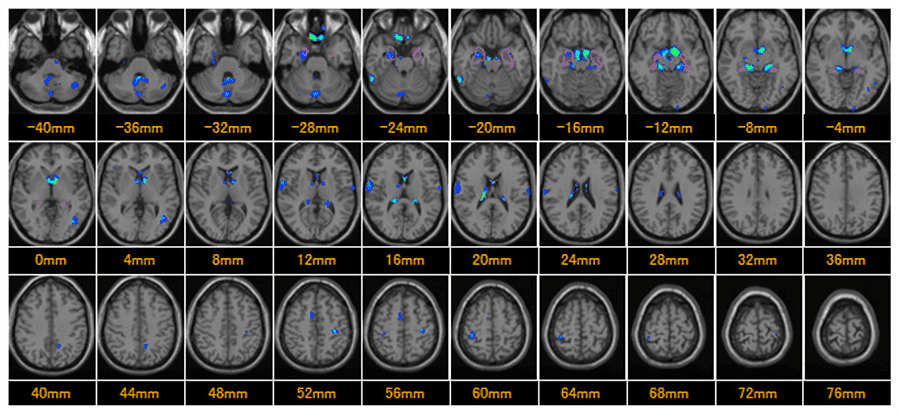

脳萎縮度検査[VSRAD]について

脳のMRI画像を利用して記憶を司る「海馬」の萎縮度を測定し、早期アルツハイマー型認知症の発症リスクを判定する検査です。正常脳との比較で評価します。

脳萎縮の強さを表す指標

| 0~1 | 脳萎縮はほとんど見られない |

| 1~2 | 脳萎縮がやや見られる |

| 2~3 | 脳萎縮がかなり見られる |

| 3~ | 脳萎縮が強い |